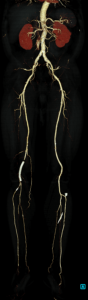

CONFIRA AS IMAGENS ABAIXO DO EXAME DE ANGIOTOMOGRAFIA VASCULAR.

Como podem ver, “conseguimos uma abrangência de vários segmentos do corpo em uma única aquisição!” – Angio Tomografia de Abdômen total e MMII (MEMBROS INFERIORES).